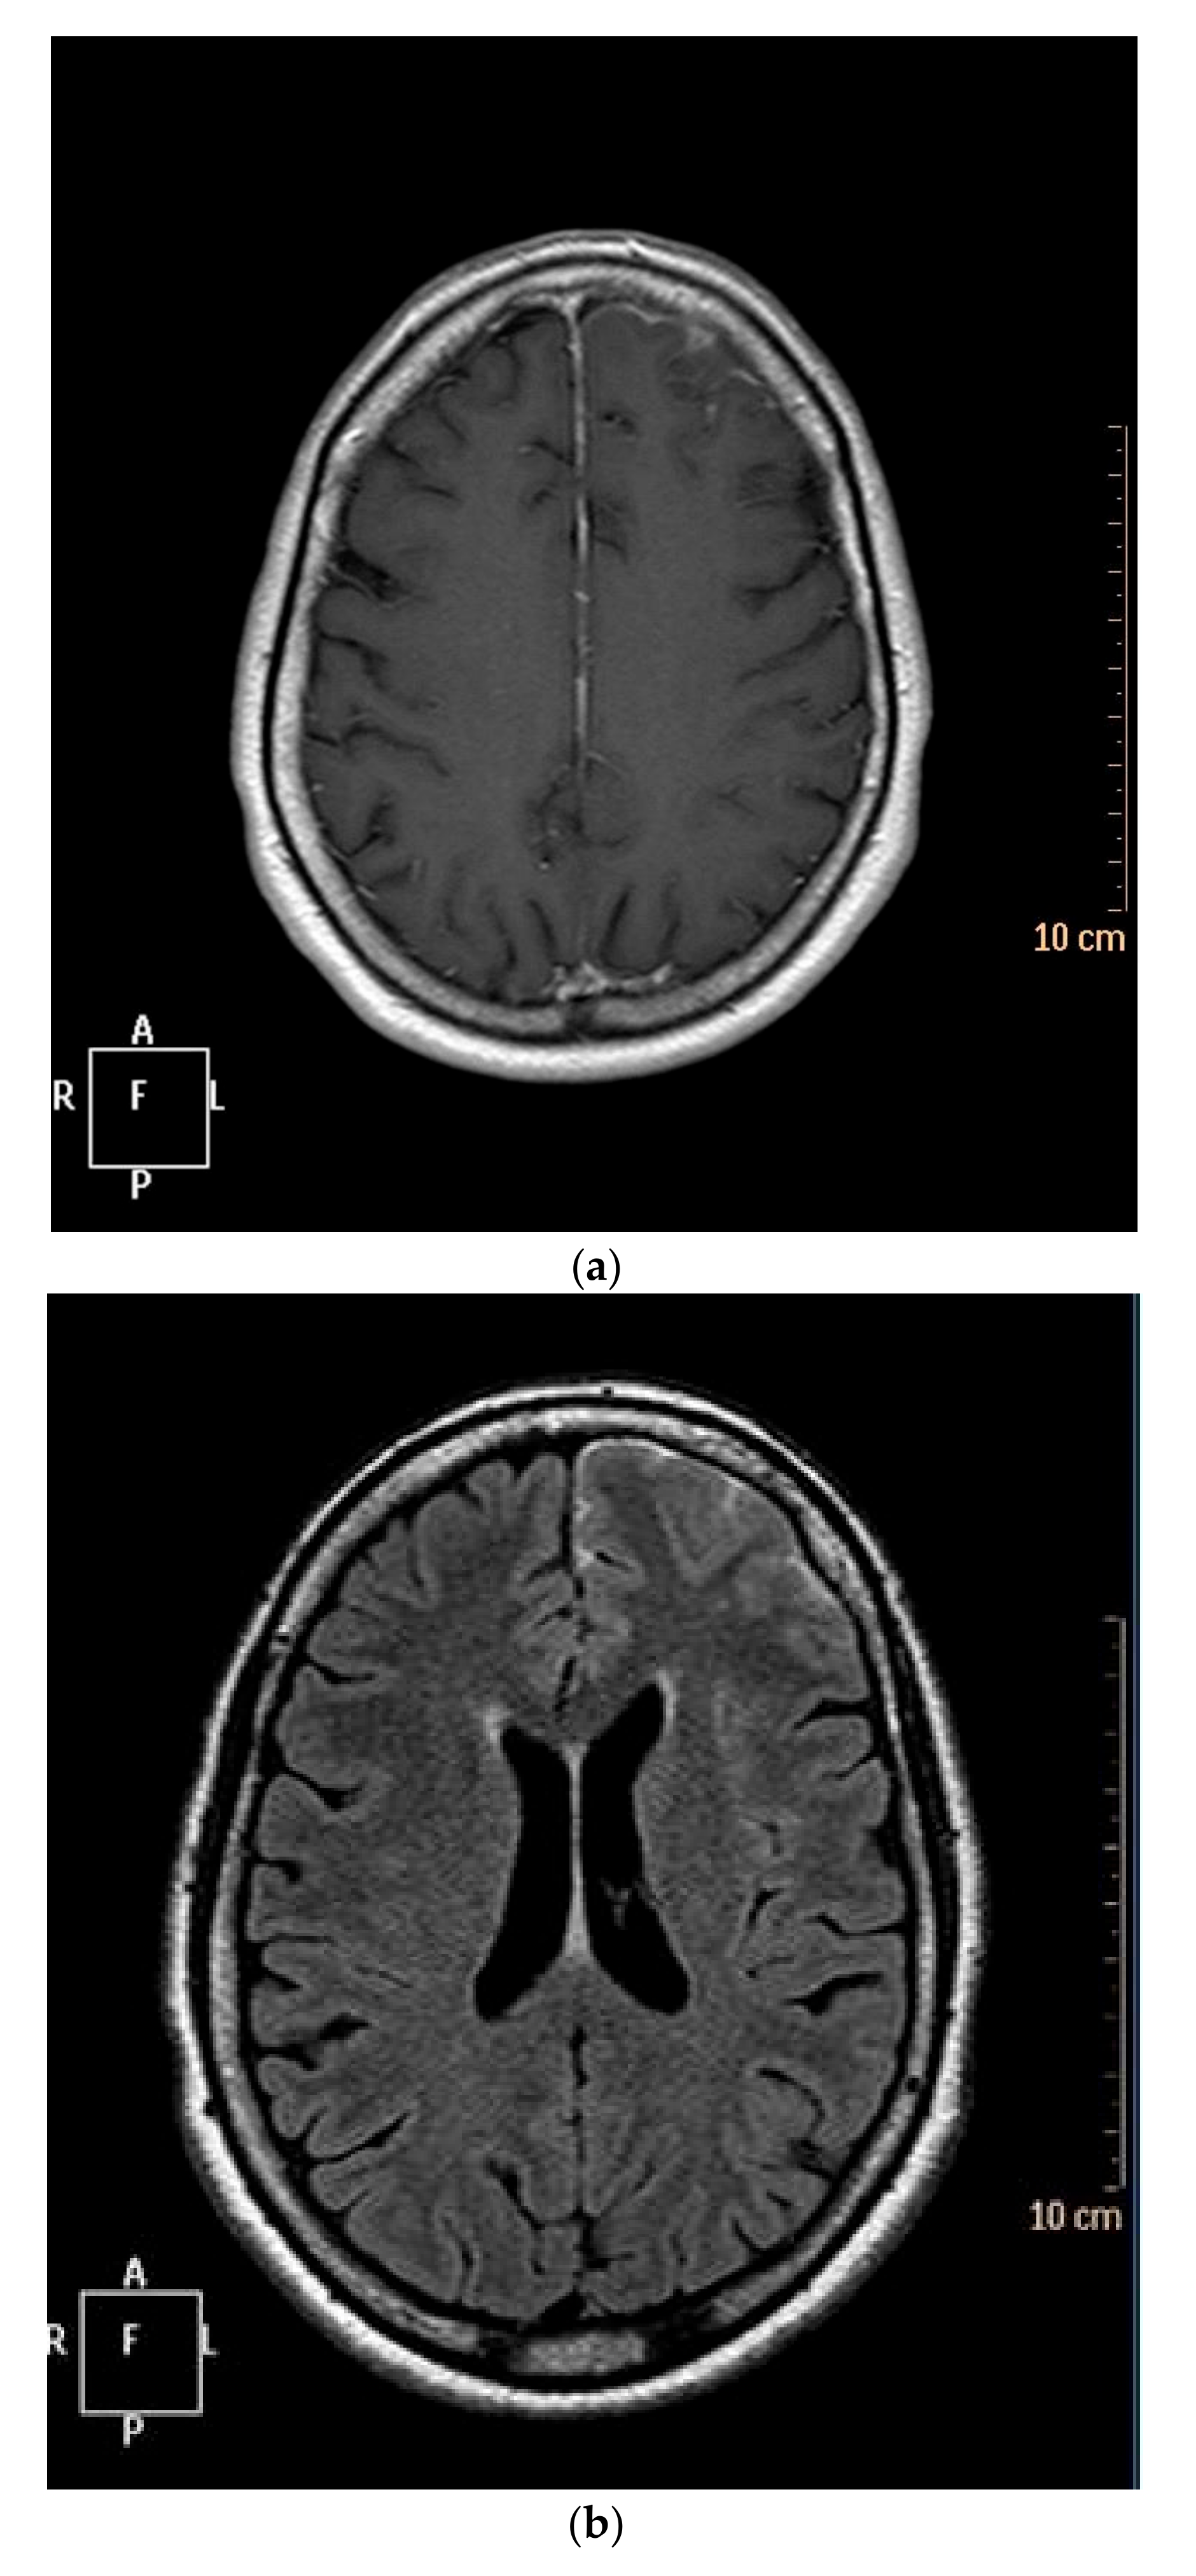

3.3. Cerebral Imaging

| 1 | F | 57 | 0.5-year history of non-erosive RA, RF-, ACPA+, RA flare, csDMARD | Generalized seizure, headaches | Hypersignal in T2-weighted images and FLAIR mode Enhancement in T1-weighted images after IV gadolinium injection | Cell count: normal Proteins concentration: normal Glycorrhachia: normal | IV steroid pulses, IV Ig | Recovery with sequelae: ongoing anticonvulsant treatment, stable chronic MRI lesions (23 months) |

| 2 | M | 69 | 7-years history of erosive RA, RF-, ACPA+, moderate RA activity, csDMARD + TNFα blocker | Headaches, frontal syndrome | Hypersignal in T2-weighted images and FLAIR mode Enhancement in T1-weighted images after IV gadolinium injection | Cell count: elevated Proteins concentration: normal Glycorrhachia: normal | IV steroid pulses, Etanercept, Rituximab | Death by subarachnoid hemorrhage (6 weeks after second Rituximab infusion) |

| 3 | F | 63 | 25-years history of non-erosive RA, RF-, ACPA+, high RA activity, csDMARD | Generalize seizure, fluctuating fever, frontal syndrome, delirium, depression-anxiety syndrome | Hypersignal in T2-weighted images Enhancement in T1-weighted images after IV gadolinium injection | Cell count: elevated Proteins concentration: elevated Glycorrhachia: missing data Syphilis PCR: negative | IV steroid pulses, Etanercept, Adalimumab | Neurologic sequelae, stable chronic MRI lesions (24 months) |

| 4 | F | 59 | 0.75-year history of non-erosive RA, RF+, ACPA+, RA remission, csDMARD + TNFα blocker | Headaches, psycho motor retardation | Enhancement in T1-weighted images after IV gadolinium injection | Cell count: elevated Proteins concentration: elevated Glycorrhachia: missing data M. tuberculosis PCR: negative | IV steroid pulses, Rituximab | Recovery with sequelae: ongoing anticonvulsant treatment, variable headaches, minor psycho motor retardation (11 months) |

| 5 | M | 50 | 7-years history of erosive RA, RF+, ACPA+, moderate RA activity, csDMARD | Focal then generalized seizure, fever, alteration of the general state, dizziness with loss of consciousness, coma | Hypersignal in T2-weighted images Hyposignal in T1-weighted images without enhancement after injection | Cell count: elevated Proteins concentration: elevated Glycorrhachia: normal HIV PCR: negative | Only usual oral steroids | Recovery with sequelae: ongoing anticonvulsant treatment, stable chronic MRI lesions (10 years) |

| 6 | F | 64 | 2-years history of non-erosive RA, RF-, ACPA+, low RA activity, no treatment | Seizure, fever, headaches, abnormal movements of the lower limb | Hypersignal in T2-weighted images and FLAIR mode Enhancement in T1-weighted images after IV gadolinium injection | Cell count: elevated Proteins concentration: normal Glycorrhachia: normal M. tuberculosis and Whipple PCR: negative | IV steroid pulses | Clinical and MRI recovery, stop anticonvulsant drugs (24 months) |